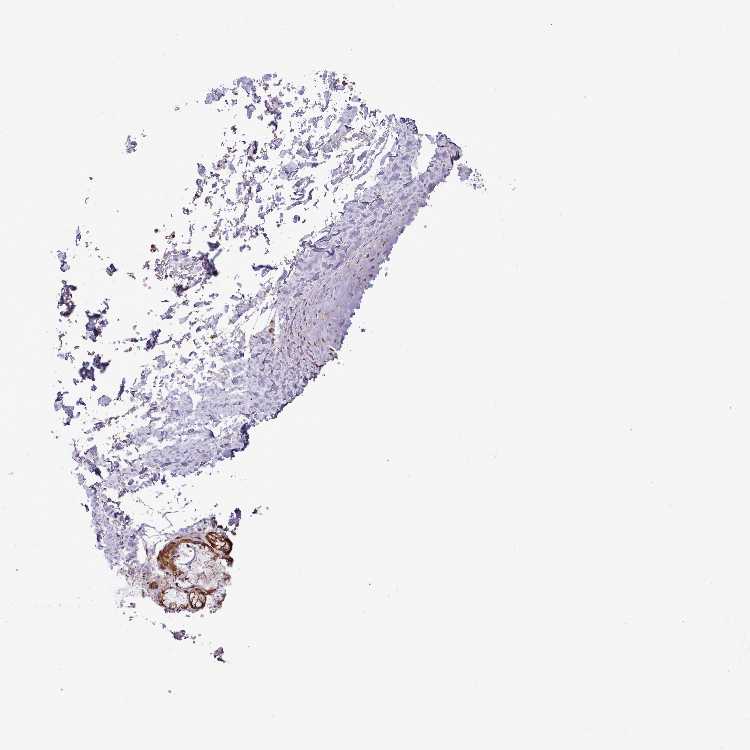

SOFT TISSUE 1 - Antibody stainingi

Antibody staining in the annotated cell types in the current human tissue is reported as not detected, low, medium, or high, based on conventional immunohistochemistry profiling in selected tissues. This score is based on the combination of the staining intensity and fraction of stained cells.

Each image is clickable and will lead to virtual microscopy that enables deeper exploration of all samples and also displays staining intensity scores, fraction scores and subcellular localization as well as patient and tissue information for each sample.

Antibody HPA050166Antibody HPA076046

Chondrocytes -Not detected

Fibroblasts MediumNot detected

Peripheral nerve HighNot detected